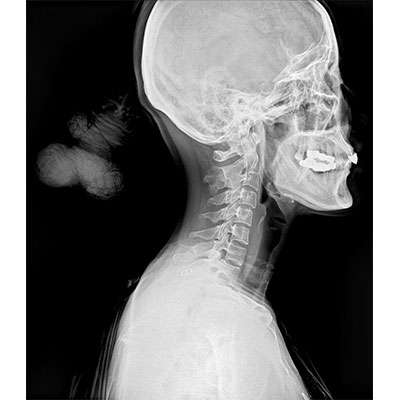

● 采用自主研發(fā)的技術(shù),在保證優(yōu)質(zhì)圖像的前提下,大大降低X射線劑量,用心呵護(hù)醫(yī)護(hù)工作者及患者的健康。

● 短曝光時間,便于老年人、兒童、殘疾人進(jìn)行臨床拍攝。避免這類群體因不能有效控制身體運(yùn)動等因素造成的運(yùn)動偽影,提高攝片質(zhì)量及效率。